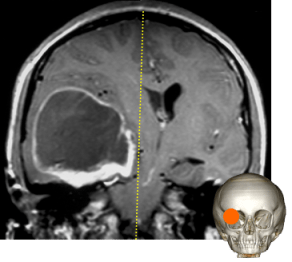

l’engagement sous-falcoriel

il traduit une compression importante avec ischémie par compression de l’artère péricalleuse homolatérale, voire bilatérale, contre le bord libre de la faux du cerveau.

dans les hématome sous-duraux, le rapport entre la surface à la convexité et celle à l’intérieur du bord libre de la faux est à l’origine d’un un levier multiplicateur de l’engagement.

cliniquement, il s’agit d’un tableau d’HTIC sévère qui n’a pas de caractère spécifique mais qui comporte un risque important de séquelles neuropsychologiques (lésions frontales bilatérales).